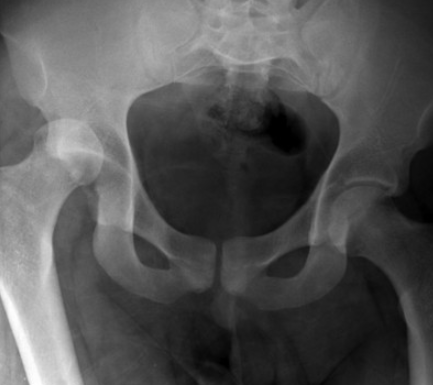

Luxation de Hanche

Antérieure

Se Rapproche du foramen obturateur

Postérieur

Se déplace supérieurement